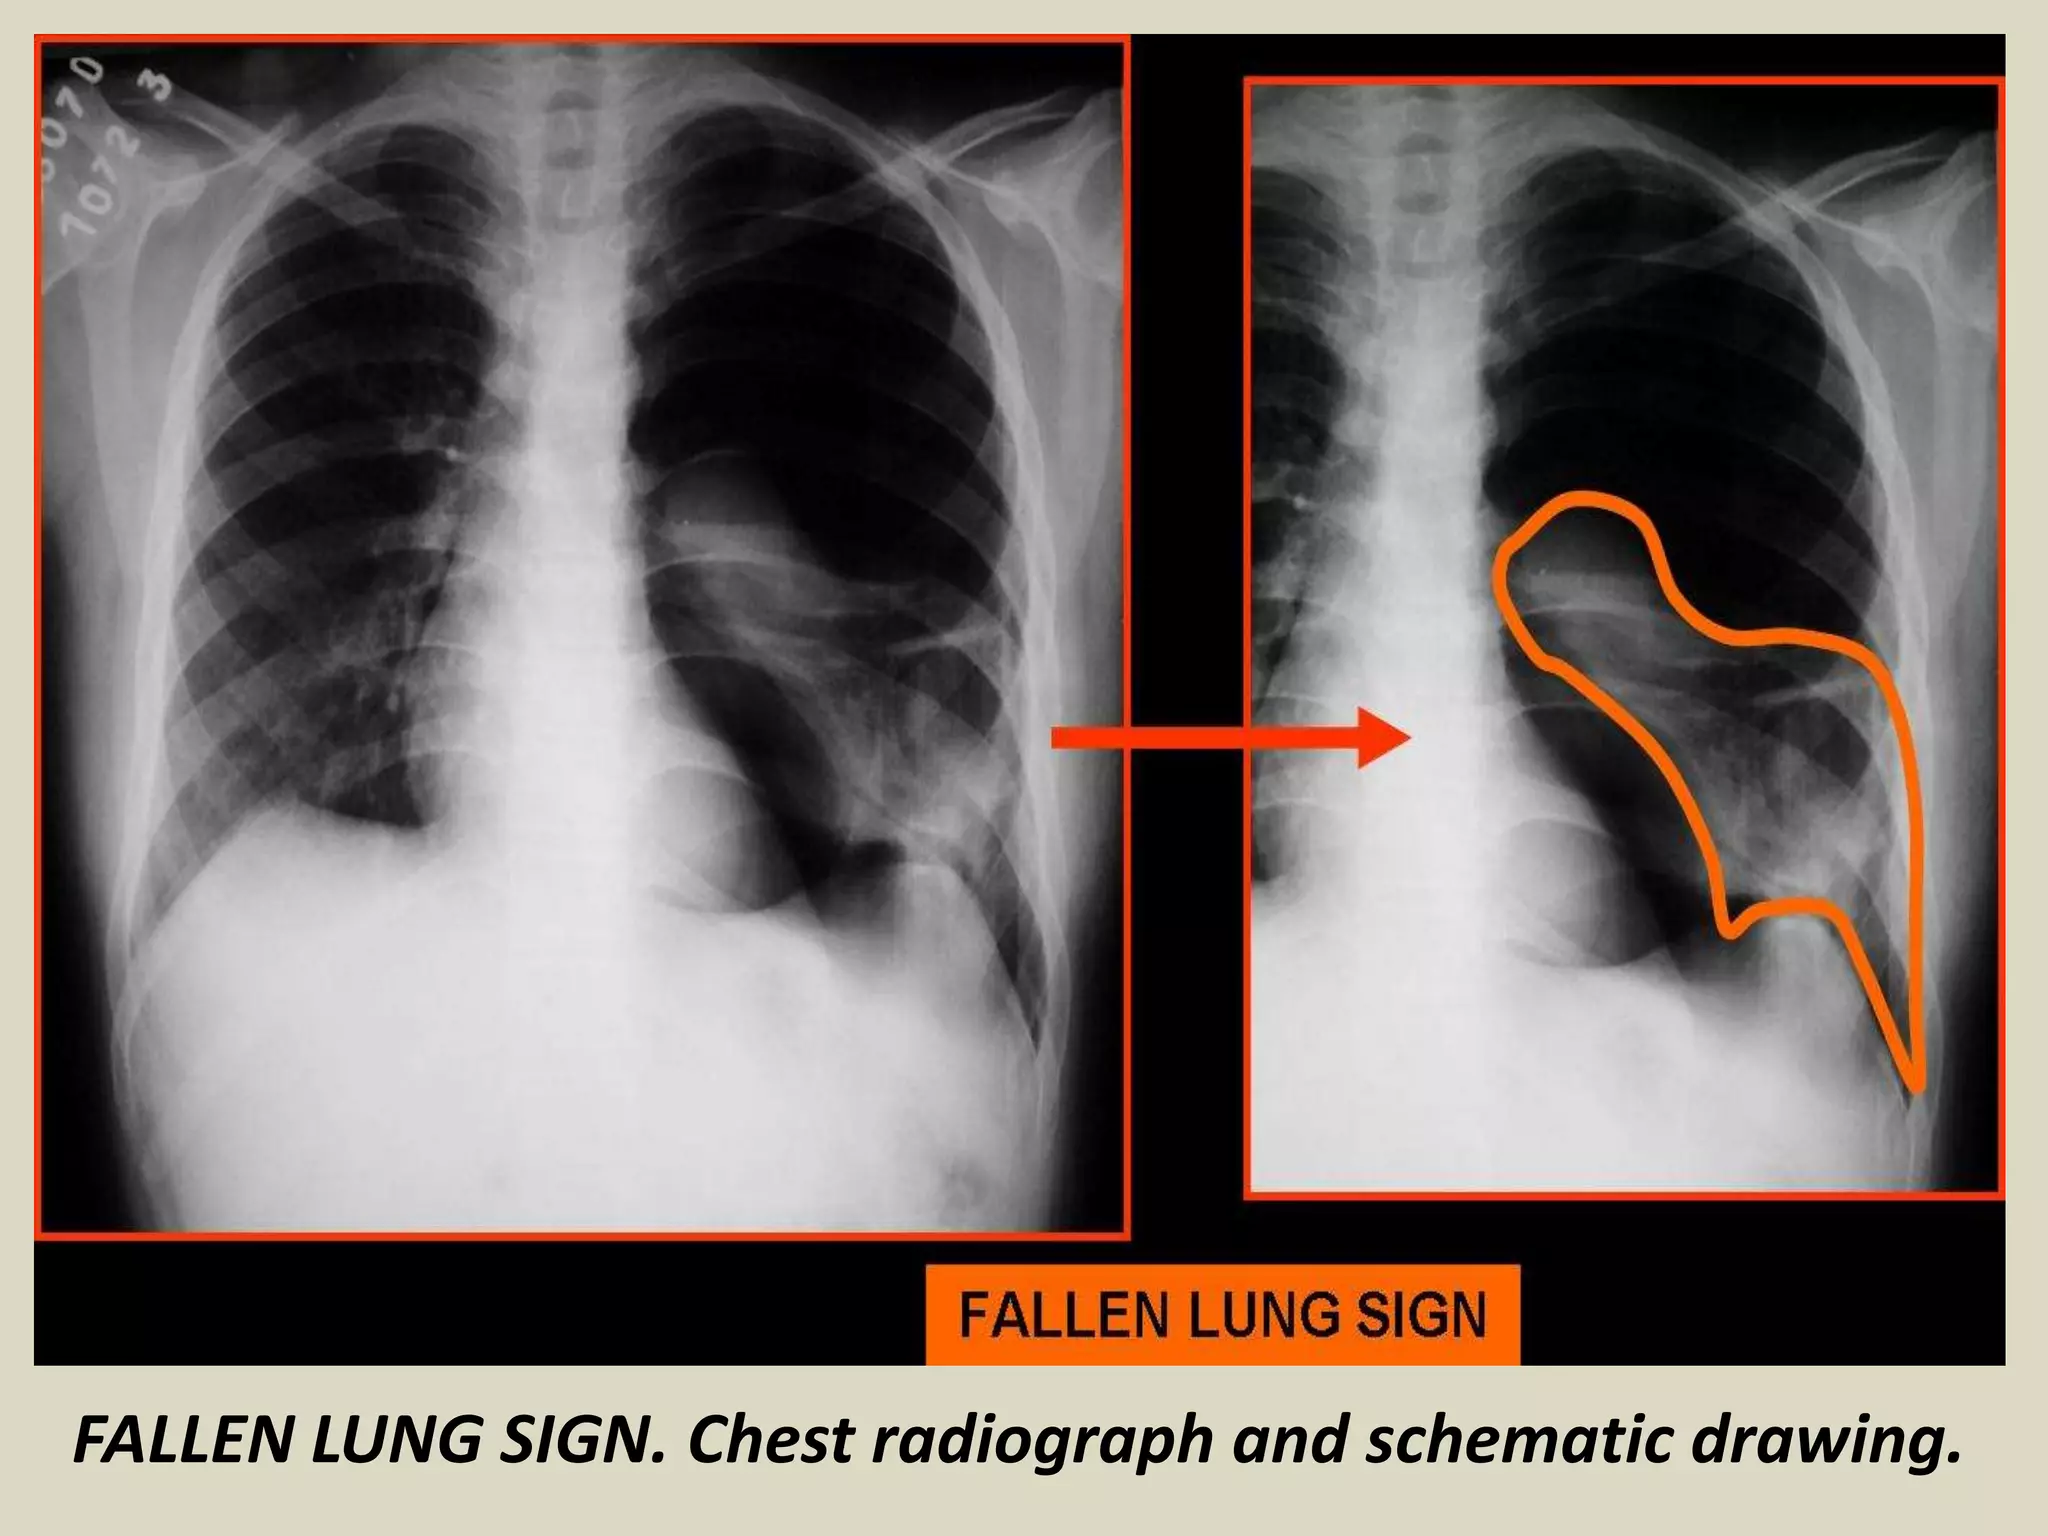

FALLEN LUNG SIGN

This sign refers to the appearance of the

collapsed lung occurring with a fractured

bronchus

It refers to the collapsed lung in a dependent

position, hanging on the hilum only by its

vascular attachments and was first described by

Oh et al in 1969 and by Kumpe et al in 1970

The bronchial fracture results in the lung to fall

away from the hilum, either inferiorly and

laterally in an upright patient or posteriorly, as

seen on CT in a supine patient.

FALLEN LUNG SIGN. Chest radiograph and schematic drawing.

FALLEN LUNG SIGN. Chest radiograph and CT Scan.

FALLEN LUNG SIGN Thissign refers to the appearance of the collapsed lung occurring with a fractured bronchus It refers to the collapsed lung in a dependent position, hanging on the hilum only by its vascular attachments and was first described by Oh et al in 1969 and by Kumpe et al in 1970 The bronchial fracture results in the lung to fall away from the hilum, either inferiorly and laterally in an upright patient or posteriorly, as seen on CT in a supine patient.

• 36.

FALLEN LUNG SIGN.Chest radiograph and schematic drawing.

• 37.

FALLEN LUNG SIGN.Chest radiograph and CT Scan.